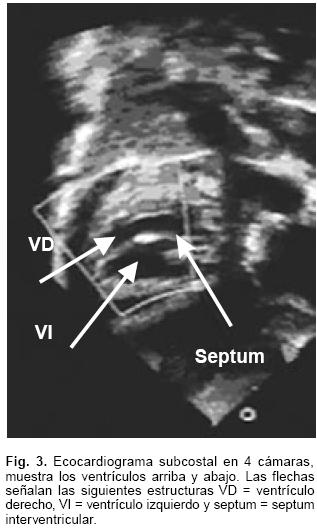

El ecocardiograma mostró foramen oval permeable, conexión atrioventricular concordante y relación atrioventricular discordante, posición superior del ventrículo derecho e inferior del izquierdo (Fig. 3); doble salida del ventrículo derecho con vasos ligeramente cruzados; estenosis subaórtica por desviación del septum infundibular; comunicación interventricular infundibular, hipoplasia del arco aórtico con una zona de coartación de tipo tubular muy estrecha y con gradiente 65 mm Hg. La presión sistólica de la arteria pulmonar (PSAP) era de 90 mm Hg. La arteria pulmonar se observó muy dilatada con datos de probable conducto arterioso persistente.

Las conexiones atrioventriculares cruzadas se establecen cuando la posición espacial de los ventrículos no concuerda con la de los atrios con quienes están conectados, de tal manera que en el presente caso el atrio derecho situado a la derecha está conectado con el ventrículo derecho ubicado espacialmente a la izquierda y viceversa.2 Es constante, aunque no patognomónica, la posición superoinferior de los ventrículos debida a la ubicación horizontal del tabique interventricular. El término crisscross refiere una relación particular entre las entradas ventriculares y no describe al corazón de manera completa.6